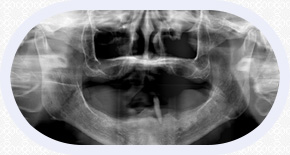

“穿颧种植术”是一种通过颧骨固定种植牙,将种植体植入到位于人面中部前,眼眶的外下方呈菱形较硬的骨头——颧骨,被种植牙界誉为“珠穆朗玛峰”的顶级技术,俗称“无土栽培术”

“穿颧种植术”受力效果好,稳定性强,可避免或减少术中大量植骨的风险,适用于上颌骨切除、上颌骨严重萎缩,常规内外提升也无法达到种植条件的无牙颌患者......查看详情